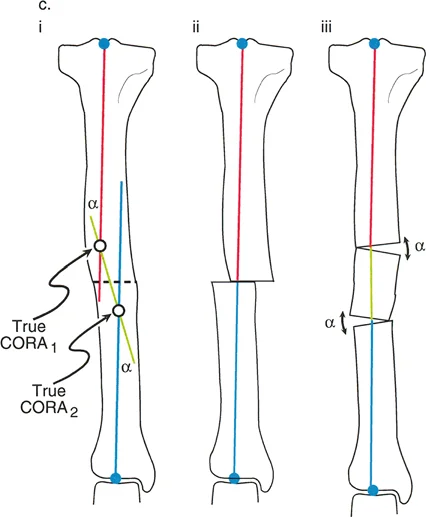

مركز دوران الانحراف (CORA)

يعتبر CORA خاصية أساسية للتشوه في العظم. يُعرّف بأنه نقطة تقاطع خط المحور الميكانيكي (أو التشريحي) القريب وخط المحور الميكانيكي (أو التشريحي) البعيد.

* CORA الحقيقي: هو القمة التشريحية الفعلية للتشوه.

* CORA الحل (Resolution CORA): نقطة نظرية تُستخدم في التشوهات متعددة المستويات حيث تتقاطع المحاور القريبة والبعيدة النهائية، وقد لا تقع هذه النقطة داخل العظم نفسه.

محور تصحيح الزاوية (ACA)

بينما يعتبر CORA حقيقة تشريحية ثابتة، فإن ACA يقع جزئيًا تحت سيطرة الجراح. يمثل ACA النقطة المحورية التي يدور حولها الجزء البعيد من العظم لتحقيق التصحيح.

* الموضع الأمثل: يجب أن يكون ACA موجهًا بشكل عمودي على مستوى التشوه ويمر مباشرة عبر CORA.

مستوى قطع العظم (Osteotomy Level)

مستوى قطع العظم (الشق الجراحي) يقع بالكامل تحت سيطرة الجراح. تحدد العلاقة الهندسية بين مستوى قطع العظم، وACA، وCORA النوع الدقيق للتصحيح الناتج، وتحدد ما إذا كان سيحدث تشوه ثانوي غير مقصود (مثل الانزياح غير المرغوب فيه).

إن فهم العلاقة المكانية بين القطع، والمفصلة، وقمة التشوه هو سر التصحيح الخالي من العيوب. تحدد قواعد بالي لقطع العظم النتائج الميكانيكية لخطتك الجراحية:

القاعدة الذهبية الأولى: القطع والمفصلة عند مركز الانحراف

عندما يمر كل من قطع العظم وACA مباشرة عبر CORA، يتم تصحيح التشوه الزاوي بشكل مثالي. يتم استعادة المحور الميكانيكي، ولا يوجد انحراف في المحور الميكانيكي (MAD)، وتبقى أجزاء العظم القريبة والبعيدة متوازية تمامًا. هذا هو السيناريو المثالي، والذي غالبًا ما يتحقق بقطع عظم وتدي بسيط (فتح أو إغلاق) عند قمة التشوه.

القاعدة الذهبية الثانية: المفصلة عند مركز الانحراف والقطع بمستوى مختلف

في بعض الأحيان، قد يكون قطع العظم مباشرة عند CORA غير ممكن سريريًا بسبب سوء حالة الجلد، أو وجود أدوات جراحية سابقة، أو مشاكل في جودة العظم في منطقة الكردوس/الجذع. إذا بقي ACA عند CORA، ولكن تم إجراء قطع العظم عند مستوى مختلف (أقرب أو أبعد عن CORA)، فسيتم تصحيح التشوه الزاوي بالكامل. ومع ذلك، ستنزاح نهايات العظم عند موقع قطع العظم بالنسبة لبعضها البعض.

* النتيجة السريرية: يؤدي هذا إلى "نتوء" أو تعرج في المحور التشريحي، لكن المحور الميكانيكي العام وتوجيه المفصل يظلان متوائمين تمامًا.